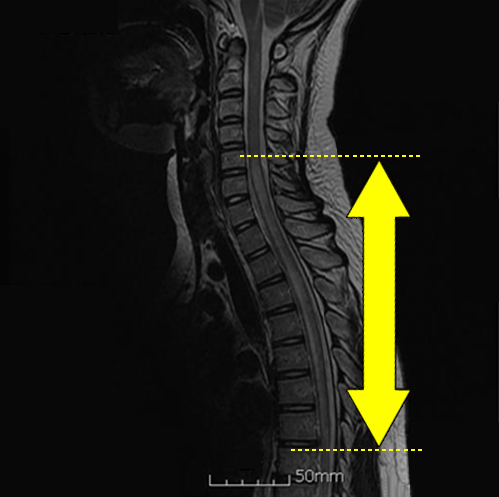

진단의 첫걸음이자 가장 중요한 단계는 신경과 전문의의 문진과 검진을 통해 이루어진다. 임상적으로 전신의 모든 검사를 하는 것은 현실적으로 불가능하기 때문에 환자의 병력이나 이학적 및 신경학적 진찰을 통해 가능한 질병과 병소를 예측하여 이에 맞게 진단에 접근하는 것은 비용적인 부분뿐 아니라 정확한 진단을 위해서 필수적이다. 병력 청취를 통해 질병의 코스나 진행 과정, 동반된 다른 관련된 질환에 대해 확인을 한 이후 이학적 및 신경학적 진찰을 통해서 가능한 신경분절을 예상하게 되고, 이에 따라 병변의 확인 및 성상에 대한 추가적인 정보를 얻기 위해 척수의 조영 증강 자기공명영상(MRI)이나 뇌척수액 검사, 때로는 유발전위검사를 시행한다. 담당의는 진찰을 통해 가능한 병변의 부위 및 원인 질환을 좁히게 되고, 이에 따라 척수병이 의심된다면 우선적으로 압박성 원인을 배제하기 위해 척수의 조영 증강을 이용한 자기공명영상(MRI)을 시행하게 된다. 압박성 원인이란 척수 외부에 종양이나 디스크, 경질막밖고름집 등으로 인해 물리적으로 척수가 밖에서부터 눌려 척수병이 생기는 경우를 말한다. 이러한 압박성 원인이 감별이 된다면, 다음으로 척수 염증성 질환을 감별하기 위해 뇌척수액검사를 시행하게 된다. 뇌척수액검사를 이용하여 염증 유무 외에도 척수염과 관련된 결핵이나 사람T세포림프친화바이러스 유형1과 유형2 등의 항체 검사를 시행하기도 한다. 이외에도 척수의 상, 하행 신경로의 기능적 손상 여부를 알아보기 위해 말단에서 전기를 자극하여 척수를 통한 신경전달에 대해 평가하는 유발전위검사를 진행하는 경우도 있다. 척수염의 경우 다발성경화증의 한 형태로 발생하는 경우도 있어 이에 대한 진단 및 재발가능성 여부를 예측하기 위해 뇌척수액검사에서 올리고클론 띠(oligoclonal band)나 면역글로불린G 지수(IgG index) 등 특수 검사를 추가하거나, 뇌 자기공명영상(MRI)이나 시야유발전위검사 등 유발전위검사를 포괄적으로 진행하기도 한다. 담당의는 진찰을 통해 가능한 병변의 부위 및 원인질환을 좁히게 되고, 이에 따라 척수병이 의심된다면 우선적으로 압박성 원인을 배제하기 위해 척수의 조영 증강을 이용한 자기공명영상(MRI)을 시행하게 된다. 압박성 원인이란 척수 외부에 종양이나 디스크, 경질막밖고름집 등으로 인해 물리적으로 척수가 밖에서부터 눌려 척수병이 생기는 경우를 말한다. 이러한 압박성 원인이 감별이 된다면, 다음으로 척수 염증성 질환을 감별하기 위해 뇌척수액검사를 시행하게 된다. 뇌척수액검사를 이용하여 염증 유무 외에도 척수염과 관련된 결핵이나 사람T세포림프친화바이러스 유형1과 유형2 등의 항체 검사를 시행하기도 한다. 이외에도 척수의 상, 하행 신경로의 기능적 손상 여부를 알아보기 위해 말단에서 전기를 자극하여 척수를 통한 신경전달에 대해 평가하는 유발전위검사를 진행하는 경우도 있다. 척수염의 경우 다발성경화증의 한 형태로 발생하는 경우도 있어 이에 대한 진단 및 재발가능성 여부를 예측하기 위해 뇌척수액검사에서 올리고클론 띠(oligoclonal band)나 면역글로불린G 지수(IgG index) 등 특수 검사를 추가하거나, 뇌 자기공명영상(MRI)이나 시야유발전위검사 등 유발전위검사를 포괄적으로 진행하기도 한다.

척수염 MRI